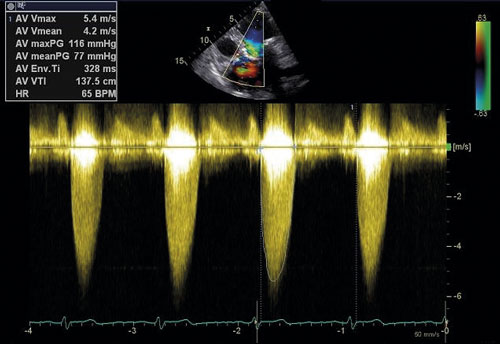

Ekokardiografi utgör en hörnsten i utredning av aortastenos (Figur 2, 3). Med kontinuerlig doppler kan tryckgradient samt medel- och maximal flödeshastighet beräknas, vilka tillsammans med uppmätt klaff­area ligger till grund för stadieindelning och prognos [10]. Utöver att visualisera klaffens grad av förkalkning ger undersökningen möjlighet att värdera övriga klaffars funktion, vänsterkammarens morfologi och funktion inklusive bestämning av ejektionsfraktion samt lungartärtryck. Transesofageal ekokardiografi kan i enstaka fall behövas för att ytterligare kartlägga anatomiska förhållanden inför exempelvis kateterburen intervention och för bättre bedömning vid samtidigt mitralisvitium [11]. Hjärtkateterisering används numera mycket sällan i diagnostiken och enbart när övriga metoder visat sig vara otillräckliga.

Figur 3. Ekokardiografi (apikal fyrrumsvy) med kontinuerlig doppler visar maximal flödeshastighet över aortaklaffen (Vmax) 5,4 m/s.